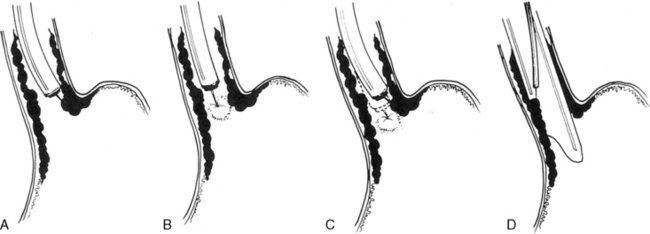

The Bianchi procedure is the oldest procedure and involves a longitudinal incision to create two tubes to lengthen the bowel (Fig. 14-5). The Kimura procedure (Fig. 14-6) is an alternative procedure for patients with SGS and inadequate mesentery who are not candidates for the Bianchi procedure. The serial transverse enteroplasty (STEP) procedure augments bowel length by stapling dilated bowel in a zigzag fashion to achieve more effective bowel surface area (Fig. 14-7).

image

Fig. 14-5 The Bianchi intestinal lengthening procedure. The bowel is divided in a longitudinal plane to create two tubes, which after reanastomosis results in doubling of the intestinal length at the expense of halving the bowel wall circumference.

(From Warner BW: Short-bowel syndrome. In Grosfeld JL et al, editors: Pediatric surgery, ed 6, Philadelphia, 2006, Mosby.)

Fig. 14-6 The Iowa (Kimura) intestinal lengthening procedure. The antimesenteric bowel wall is pexed to the undersurface of the abdominal wall. A seromyotomy along the bowel wall and mechanical abrasion of the abdominal wall before pexing promote neovascularization of the antimesenteric bowel, based on the systemic-derived abdominal wall. Several months later, the bowel may be longitudinally divided into two limbs. The first is based on the systemic blood supply to the antimesenteric limb, and the other is based on the mesenteric blood supply. These two limbs are then reapproximated to double the intestinal length.

Fig. 14-7 The serial transverse enteroplasty procedure. Multiple fires of an anastomotic stapling device to alternating sides of the bowel wall result in decreased bowel caliber with an increased length of enteral nutrient transit.